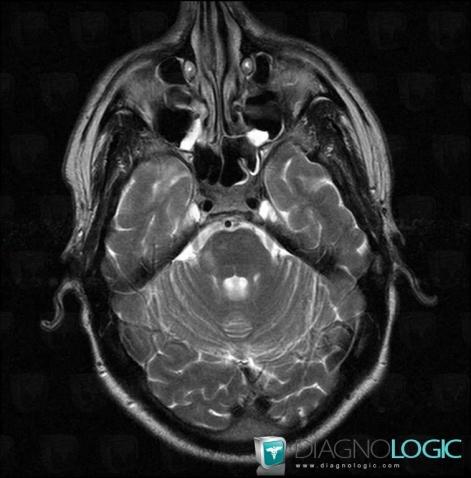

Multiple sclerosis, Brainstem, Posterior fossa, MRI

Here is the specific information in the key image above:

- Diagnosis Multiple sclerosis, Location(s) Brainstem, with gamuts Brainstem lesion, Brainstem Hyperintense T2WI or FLAIR lesionPosterior fossa, with gamuts Multifocal infratentorial lesions, Infratentorial T2W or FLAIR hyperintense lesion